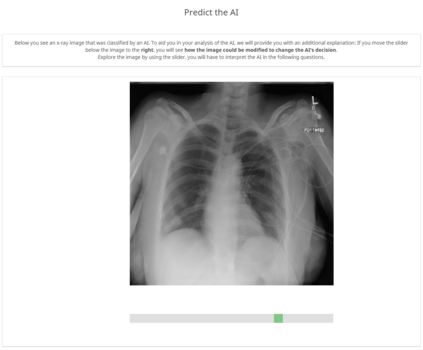

With the ongoing rise of machine learning, the need for methods for explaining decisions made by artificial intelligence systems is becoming a more and more important topic. Especially for image classification tasks, many state-of-the-art tools to explain such classifiers rely on visual highlighting of important areas of the input data. Contrary, counterfactual explanation systems try to enable a counterfactual reasoning by modifying the input image in a way such that the classifier would have made a different prediction. By doing so, the users of counterfactual explanation systems are equipped with a completely different kind of explanatory information. However, methods for generating realistic counterfactual explanations for image classifiers are still rare. Especially in medical contexts, where relevant information often consists of textural and structural information, high-quality counterfactual images have the potential to give meaningful insights into decision processes. In this work, we present GANterfactual, an approach to generate such counterfactual image explanations based on adversarial image-to-image translation techniques. Additionally, we conduct a user study to evaluate our approach in an exemplary medical use case. Our results show that, in the chosen medical use-case, counterfactual explanations lead to significantly better results regarding mental models, explanation satisfaction, trust, emotions, and self-efficacy than two state-of-the-art systems that work with saliency maps, namely LIME and LRP.